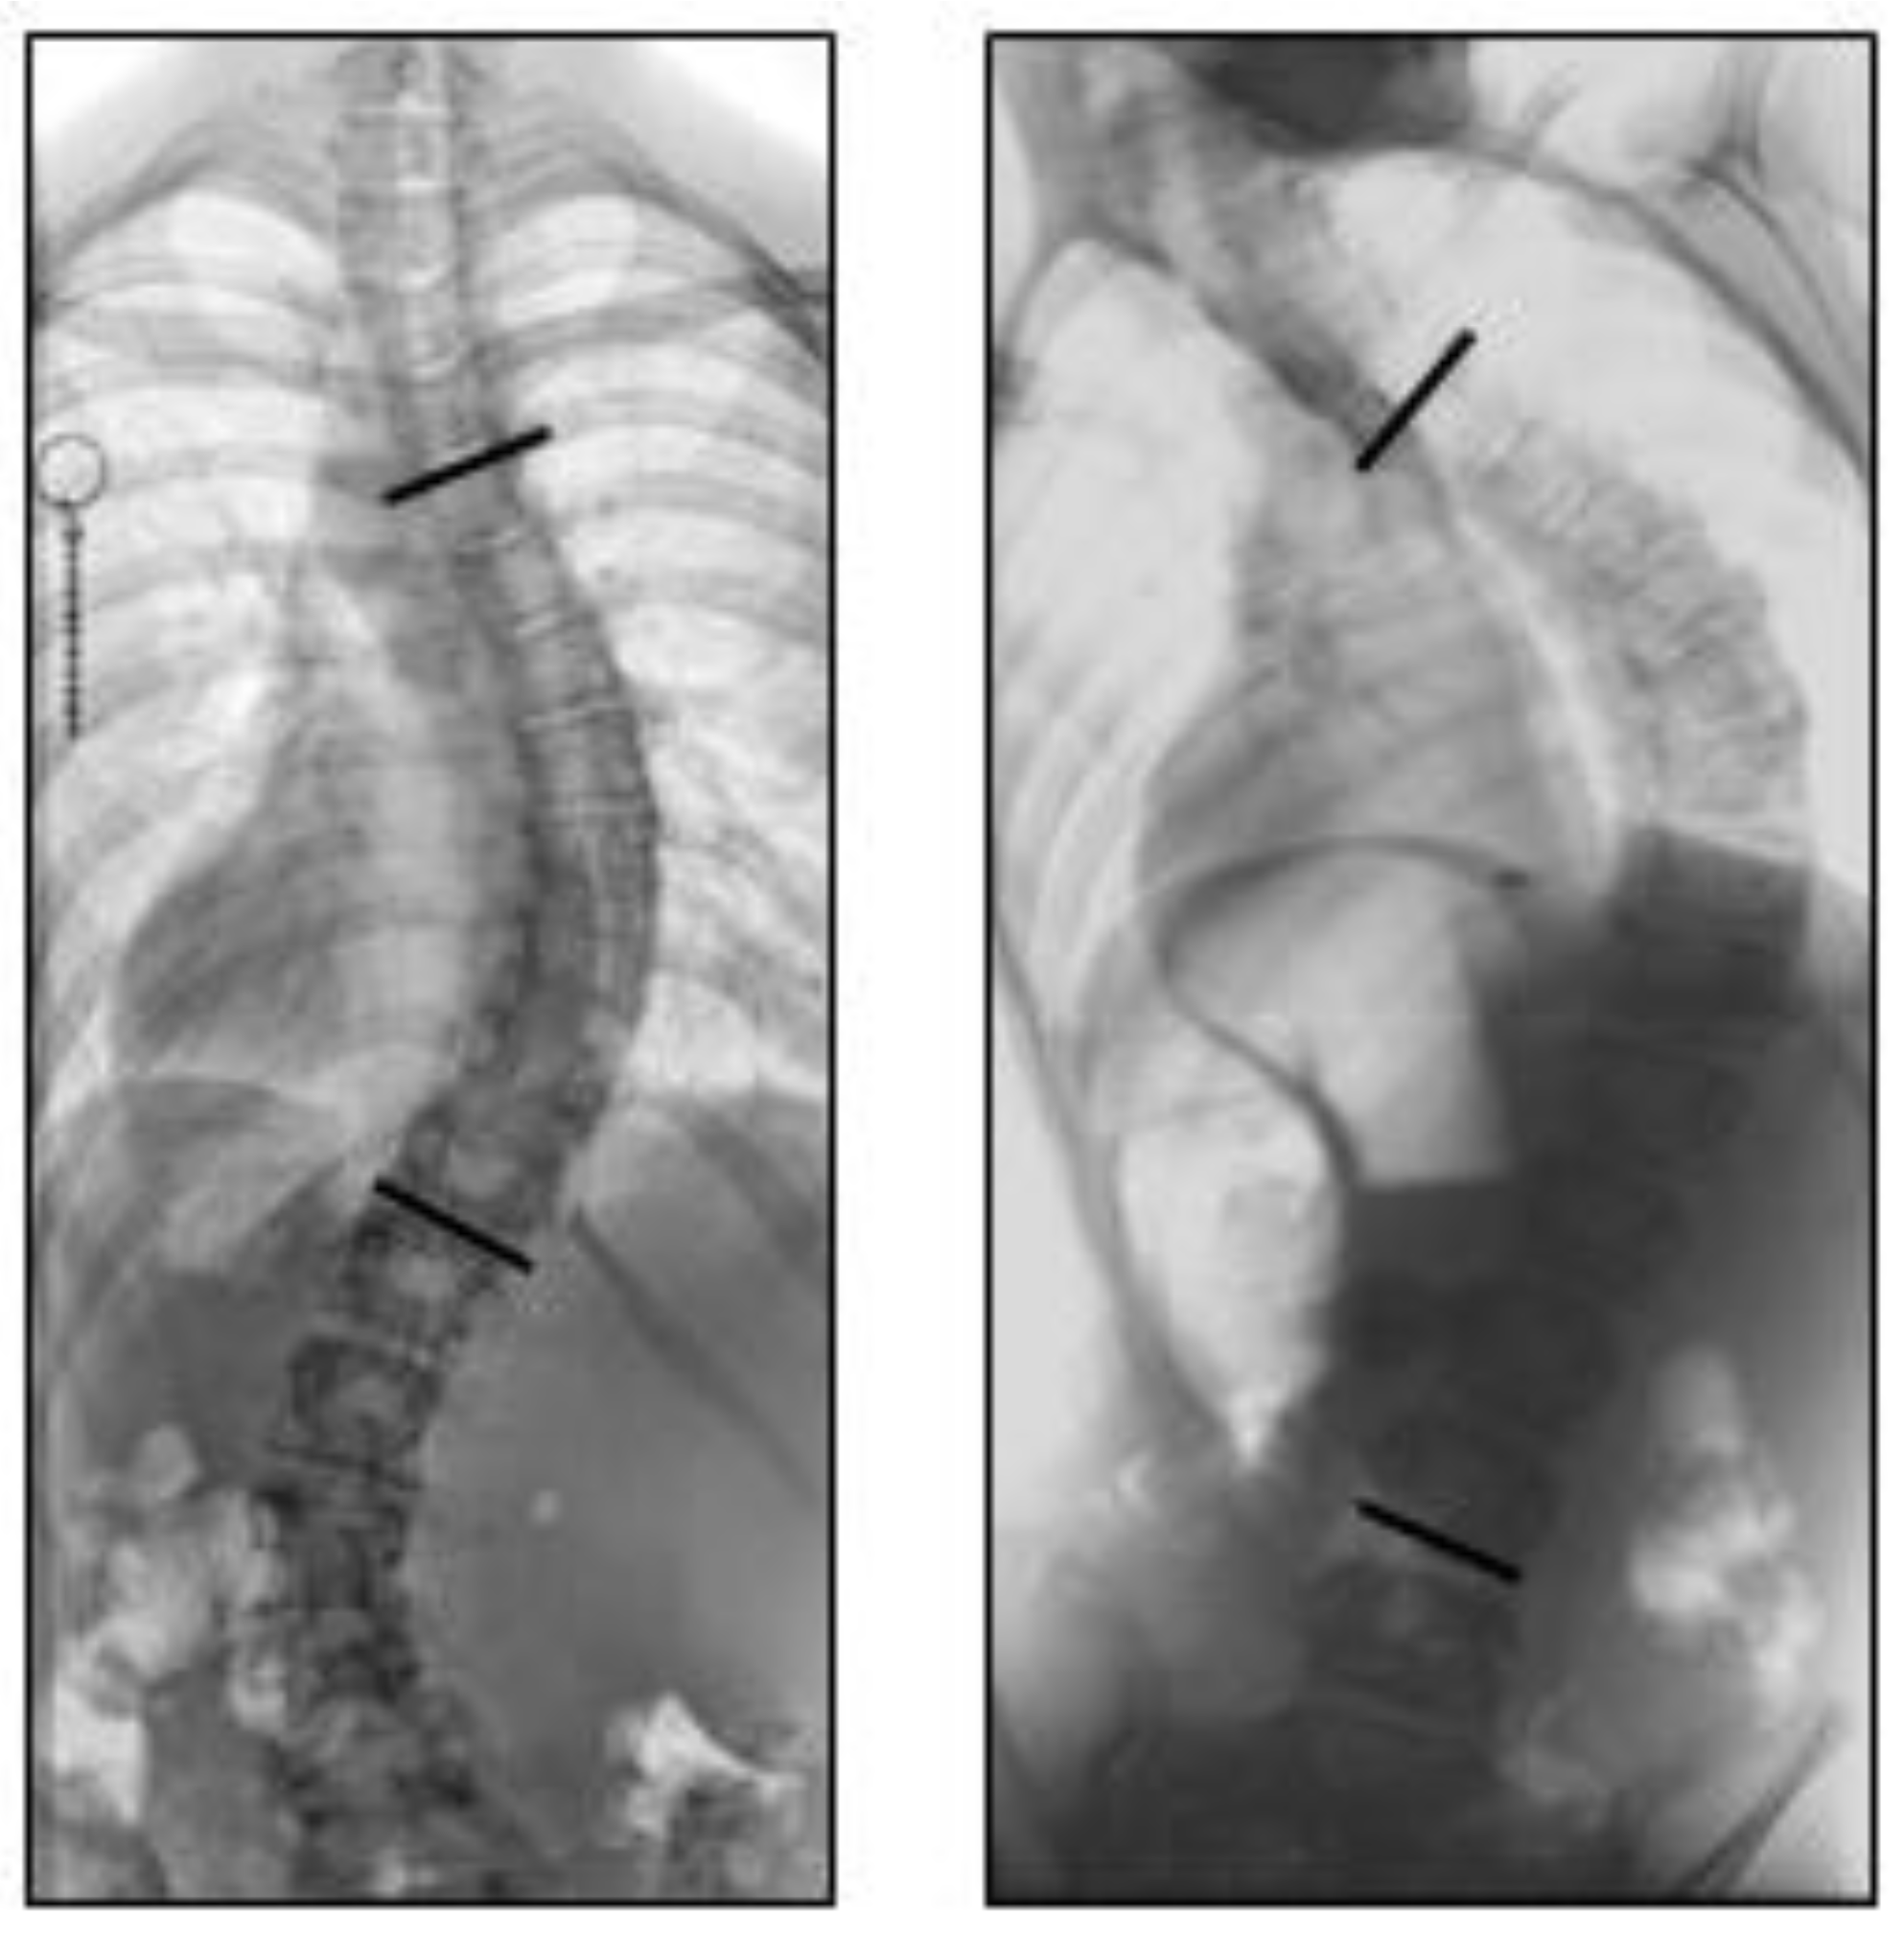

3.2. Radiographic Analysis

3.3. MRI Analysis